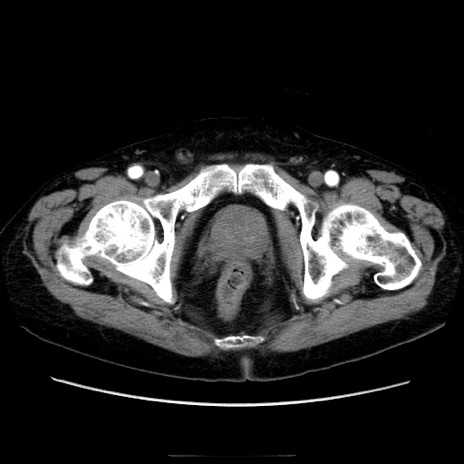

冠状断像